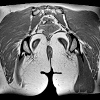

МРТ мягких тканей ягодичной области

МРТ мягких тканей ягодичной области. Диагностический процесс для послойной визуализации тканей с использованием радиоволн и сильного магнитного поля с последующей компьютерной обработкой данных. При необходимости в процессе исследования используется контрастное вещество. При необходимости уточняются данные других методов, проводится дифференциальная диагностика или устанавливается тактика хирургического вмешательства. Он проводится для оценки состояния мышц, жировой ткани, связок, сухожилий, кровеносных сосудов и нервных волокон в области ягодиц. Выполняется при объемных процессах различной этиологии, пороках развития, травмах и последствиях травм, воспалительных и инфекционных поражений, нарушениях кровообращения, признаках сдавливания нерва и синдроме интенсивной боли, устойчивых к традиционной терапии.